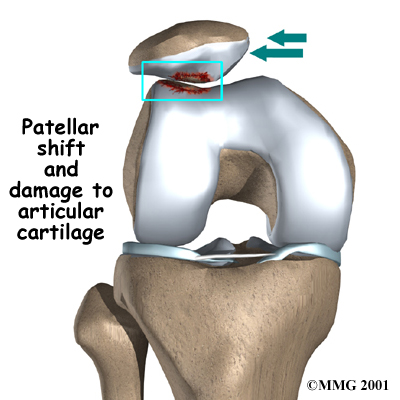

A similar problem can happen when the timing of the quadriceps muscles is off. There are four muscles that form the quadriceps muscle group. As mentioned earlier, the VMO is one of these four muscles. The VMO is the section of muscle on the inside of the front of the thigh. The VL runs down the outside part of the thigh. People with patellofemoral problems sometimes have problems in the timing between the VMO and the VL. The VL contracts first, before the VMO. This tends to pull the patella toward the outside of edge of the knee. The result is abnormal pressure on the articular surface of the patella.

Another type of imbalance may exist due to differences in how the bones of the knee are shaped. These differences, or anatomic variations, are something people are born with. Some people are born with a greater than normal angle where the femur and the tibia (shinbone) come together at the knee joint. Women tend to have a greater angle here than men. The patella normally sits at the center of this angle within the femoral groove. When the quadriceps muscle contracts, the angle in the knee straightens, pushing the patella to the outside of the knee. In cases where this angle is increased, the patella tends to shift outward with greater pressure. This leads to a similar problem as that described above. As the patella slides through the groove, it shifts to the outside. This places more pressure on one side than the other, leading to damage to the underlying articular cartilage.

Another type of imbalance may exist due to differences in how the bones of the knee are shaped. These differences, or anatomic variations, are something people are born with. Some people are born with a greater than normal angle where the femur and the tibia (shinbone) come together at the knee joint. Women tend to have a greater angle here than men. The patella normally sits at the center of this angle within the femoral groove. When the quadriceps muscle contracts, the angle in the knee straightens, pushing the patella to the outside of the knee. In cases where this angle is increased, the patella tends to shift outward with greater pressure. This leads to a similar problem as that described above. As the patella slides through the groove, it shifts to the outside. This places more pressure on one side than the other, leading to damage to the underlying articular cartilage.

Finally, anatomic variations in the bones of the knee can occur such that one side of the femoral groove is smaller than normal. This creates a situation where the groove is too shallow, usually on the outside part of the knee. People who have a shallow groove sometimes have their patella slip sideways out of the groove, causing a patellar disclocation. This is not only painful when it occurs, but it can damage the articular cartilage underneath the patella. If this occurs repeatedly, degeneration of the patellofemoral joint occurs fairly rapidly.

Finally, anatomic variations in the bones of the knee can occur such that one side of the femoral groove is smaller than normal. This creates a situation where the groove is too shallow, usually on the outside part of the knee. People who have a shallow groove sometimes have their patella slip sideways out of the groove, causing a patellar disclocation. This is not only painful when it occurs, but it can damage the articular cartilage underneath the patella. If this occurs repeatedly, degeneration of the patellofemoral joint occurs fairly rapidly.